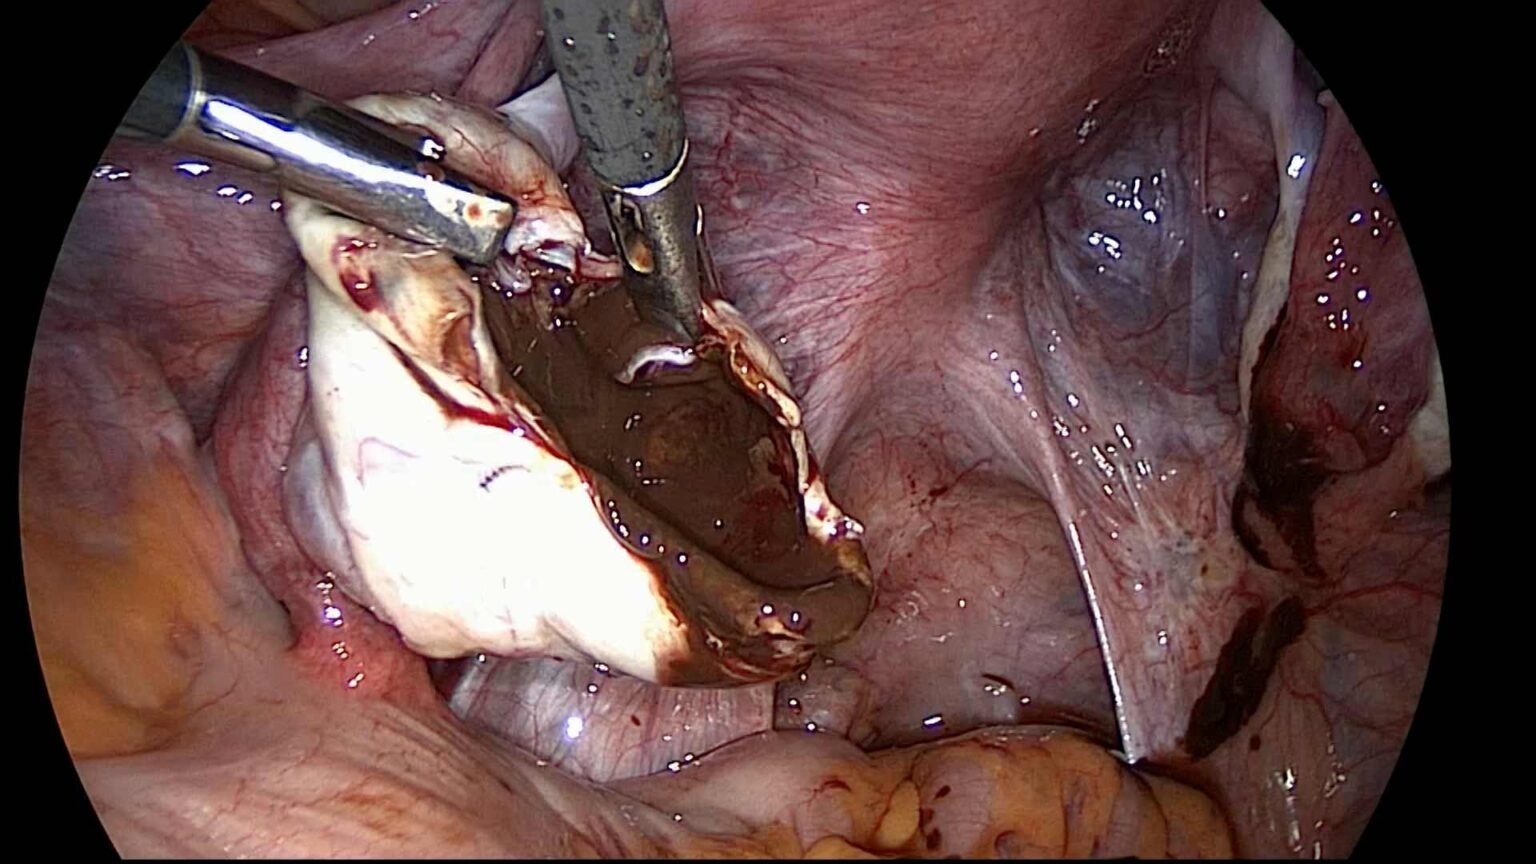

Uno dei principali vantaggi della chirurgia laparoscopica è la migliore visualizzazione dei dettagli anatomici offerta dalle ottiche di ultima generazione in alta definizione. Questo permette ai chirurghi di avere una visione chiara e dettagliata dell’area operativa, consentendo una maggiore precisione nei movimenti e una migliore identificazione delle strutture anatomiche coinvolte.

Inoltre, l’utilizzo di ottiche in 3D consente una percezione tridimensionale dell’area operativa, migliorando ulteriormente la precisione e facilitando la navigazione attraverso i tessuti. Questo contribuisce a una maggiore sicurezza durante l’intervento e una migliore identificazione delle piccole strutture anatomiche.